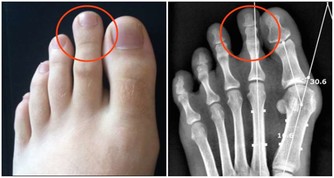

●膝蓋退化了沒!中醫師蔡曜鍵教你自行檢測,還要提供養膝茶飲!還 不快抄起來。